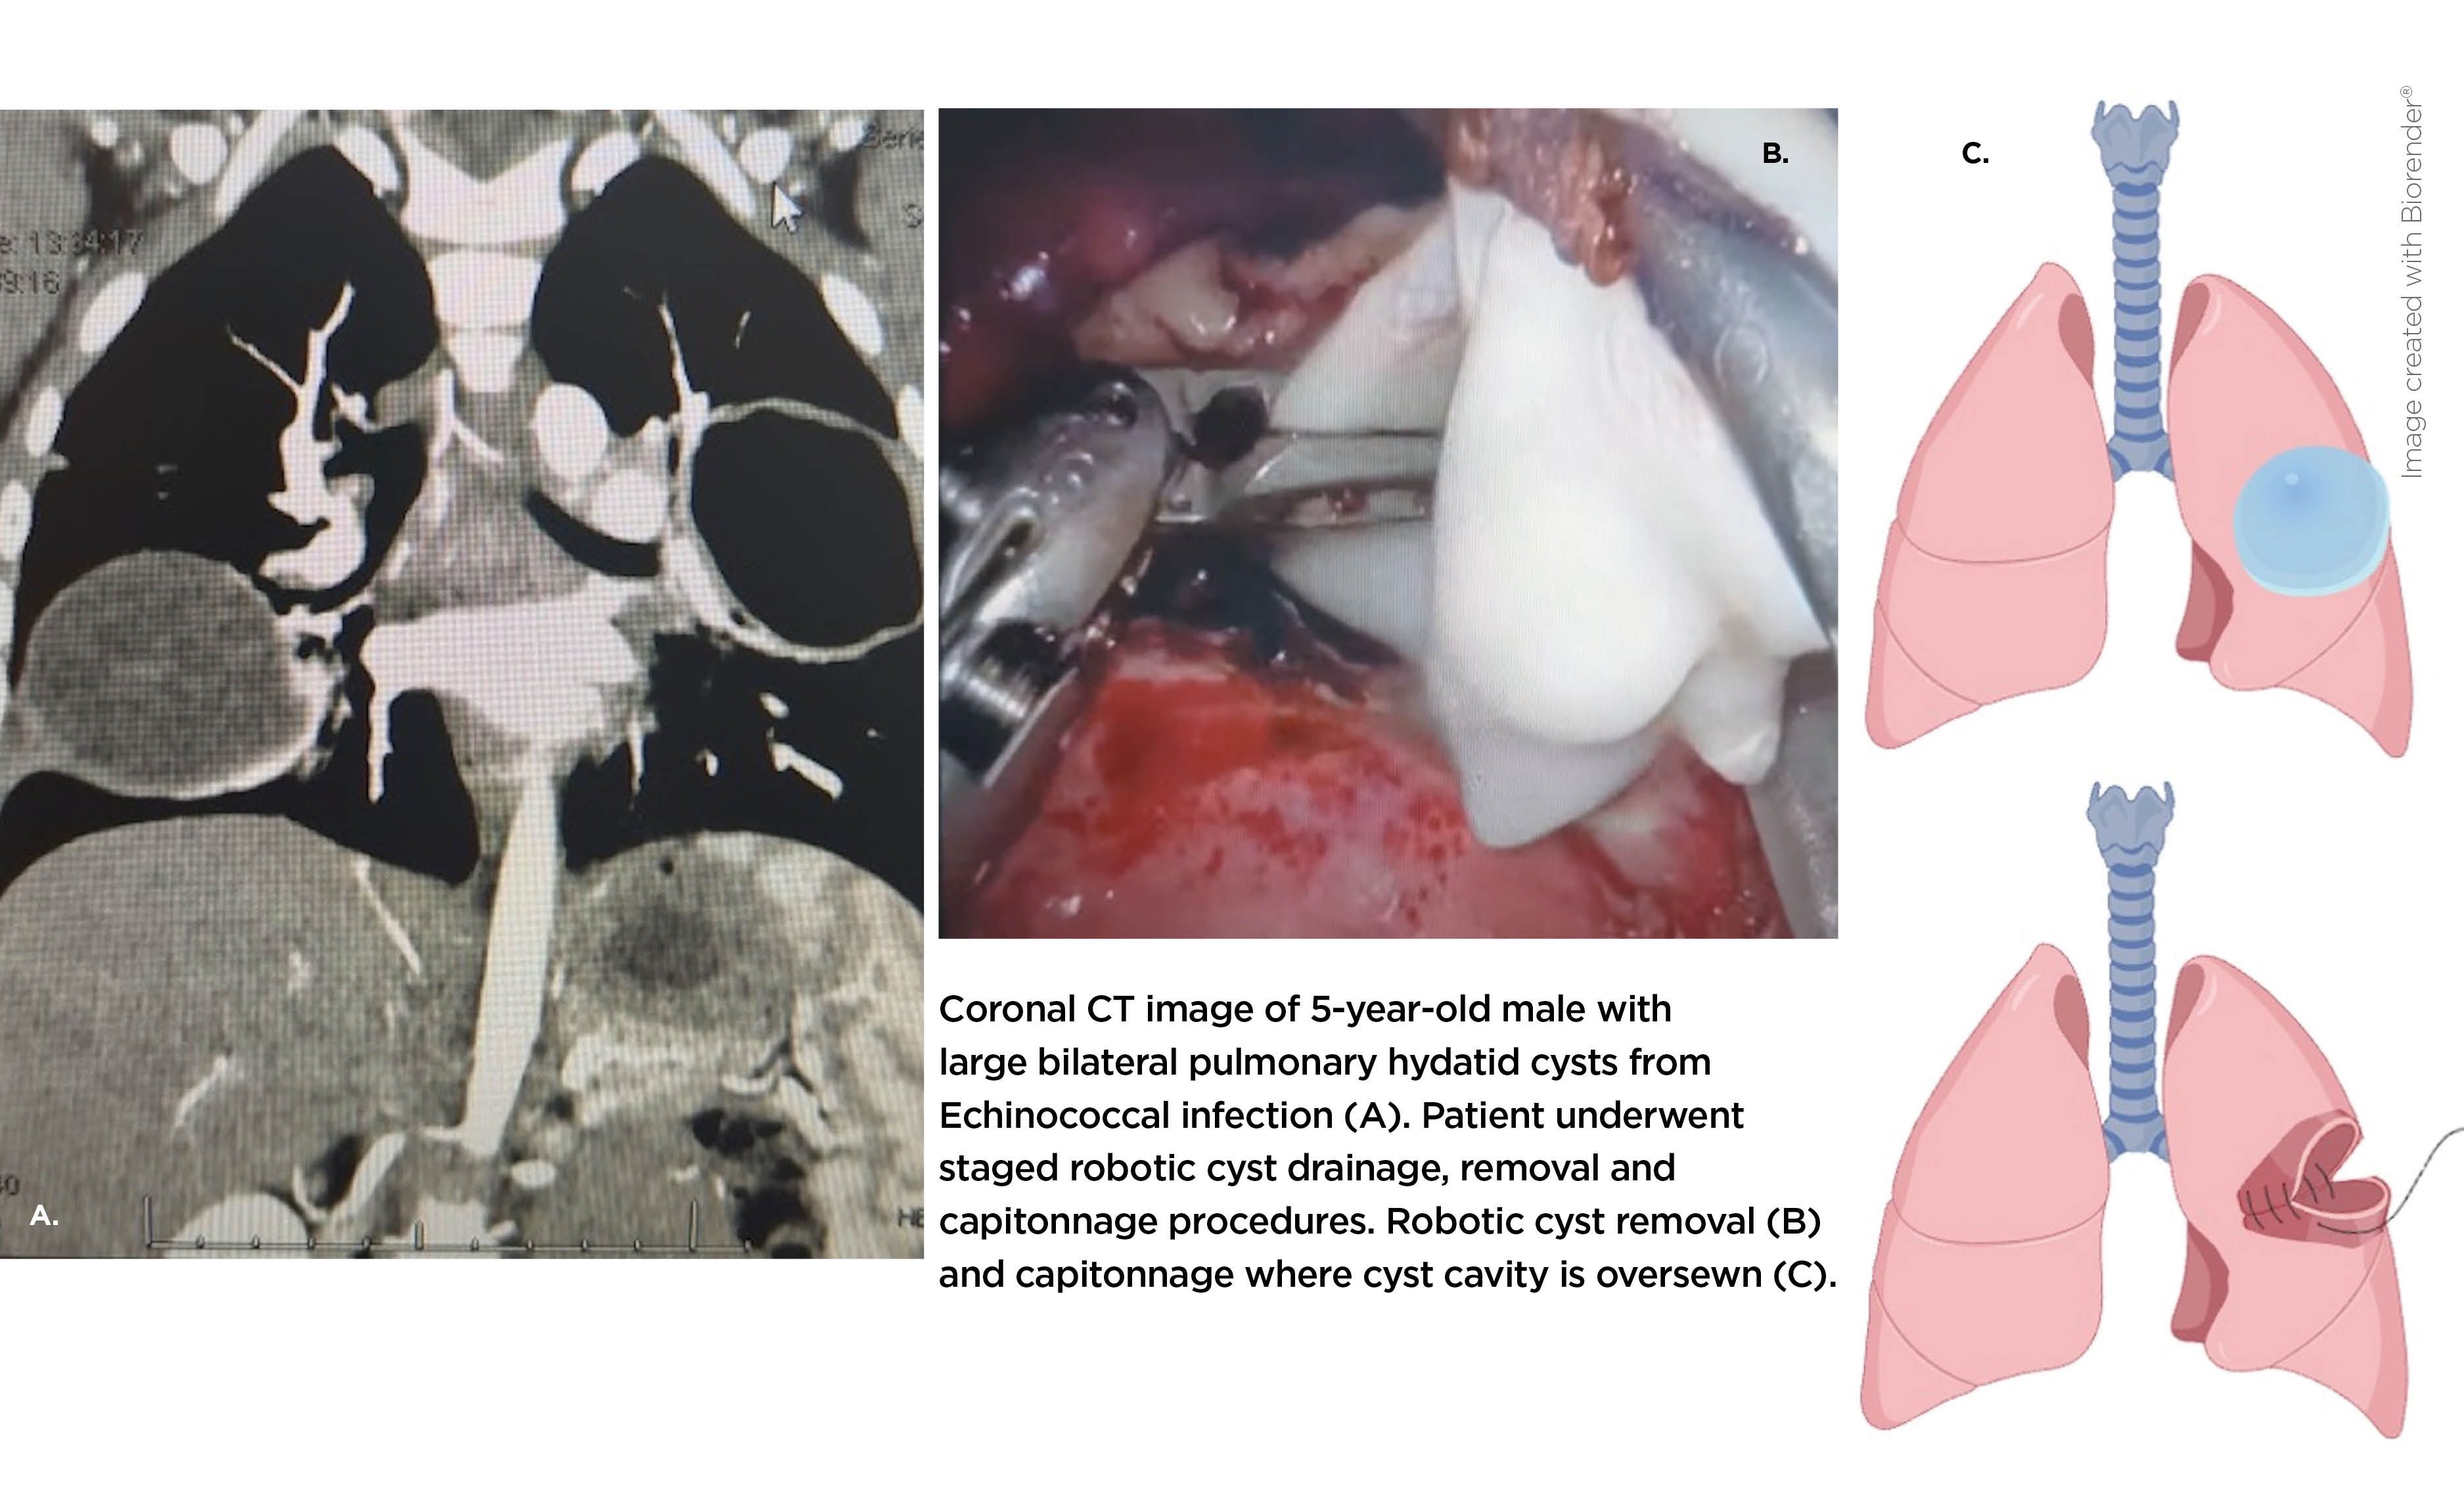

Between April 2024 and July 2025, our team completed 10 collaborative pediatric robotic thoracic surgeries, including eight performed at Children’s Wisconsin. Among them were three lung surgeries for echinococcal hydatid cysts in two children with bilateral disease, representing the youngest reported patients treated robotically for this condition.